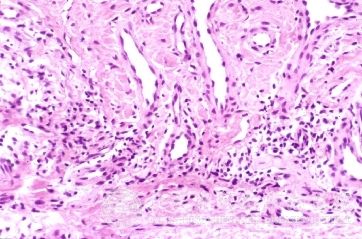

北京京城皮肤医院指出:神经瘙痒性皮炎要及时治疗。

神经瘙痒性皮炎是皮炎类型中的一种,它的出现给人们的肌肤造成了非常严重的损害现象,为此务必要及时的进行治疗。不过有很多人由于对神经瘙痒性皮炎的症状不是了解,为此没有及时发现与治疗,较终导致病情的严重性。